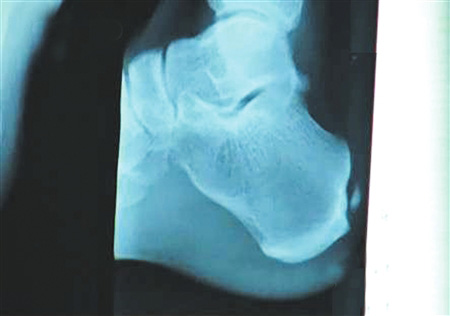

手術(shù)要取出的鈣化物就在這里。 圖片來(lái)源:華西都市報(bào)